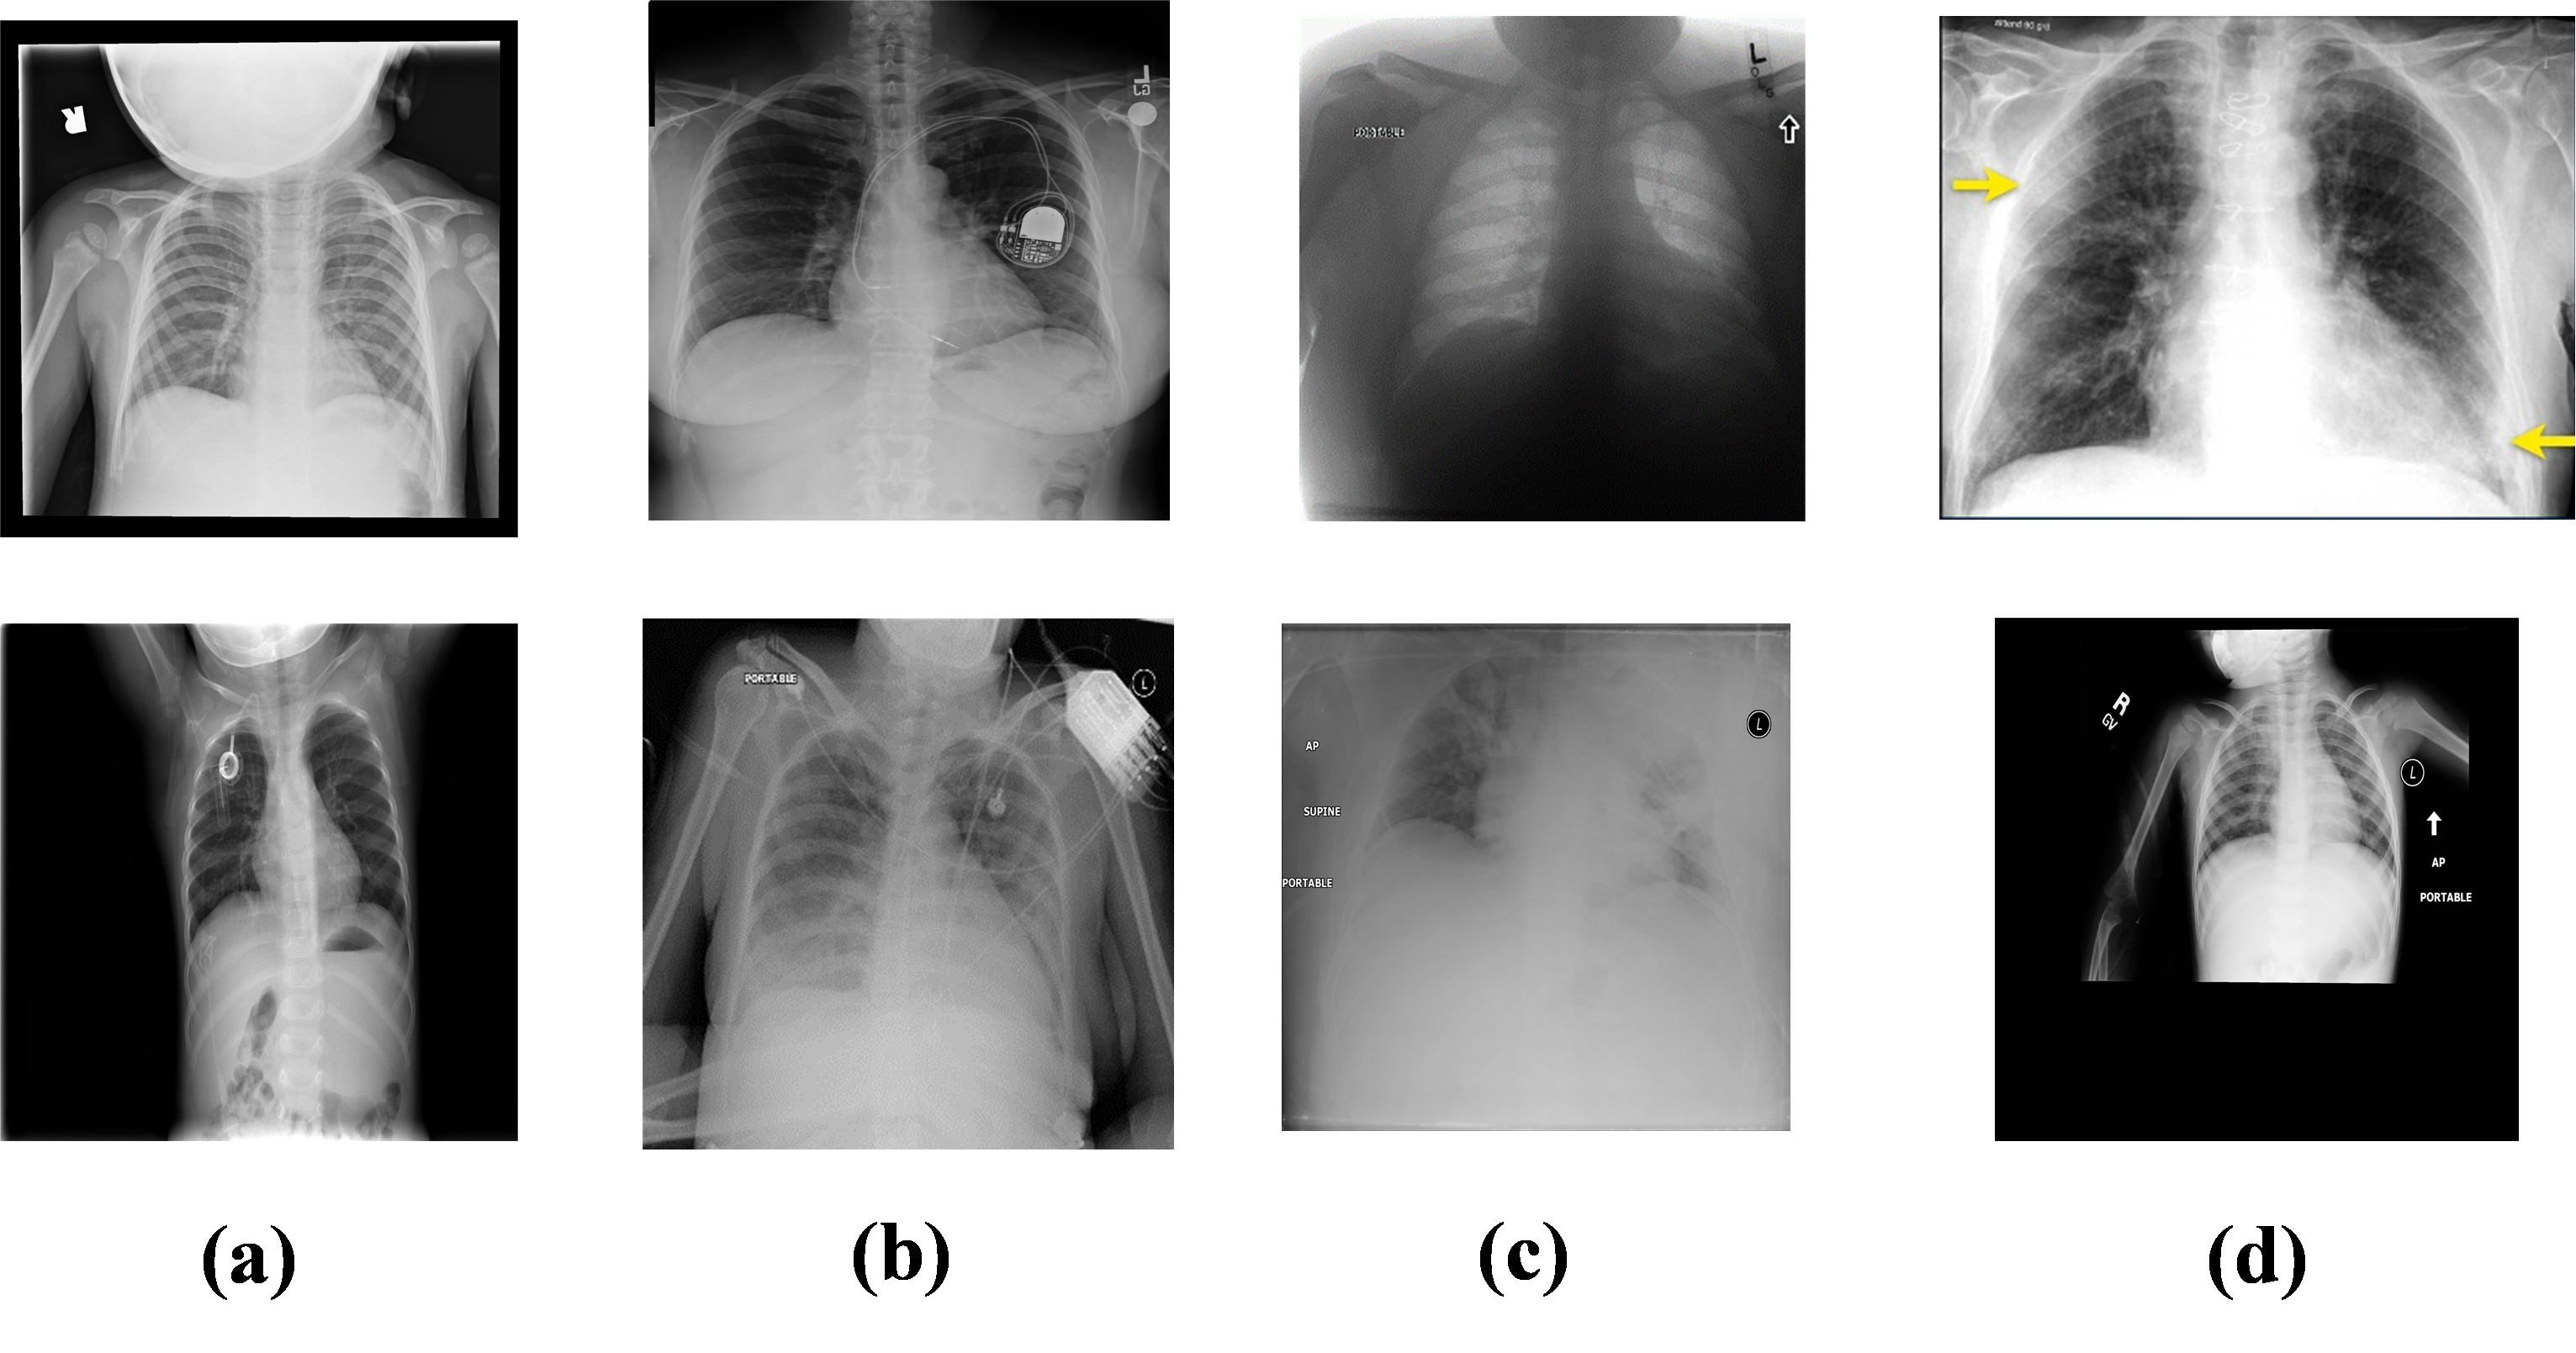

Thirdly, characteristics associated with each CXR image data set also affect model performance. For example, COVIDx is an open-access benchmark data set and it comprises 16,3521635216,352 CXR images from a multinational cohort of 15,3461534615,346 patients from at least 51 countries [12]. Like other CXR databases, the COVIDx data set contains a considerable number of images with peculiarities, some of which are demonstrated in Fig. 1. Body parts, including a patient’s head, hands, and abdomen, are often captured in pediatric CXR images (Fig. 1-a). Foreign objects such as implanted devices and wires appear in CXR images (Fig. 1-b). Some images are under-penetrated radiographs (Fig. 1-c). In addition, there are cases where the lung is surrounded by a black box and/or with the presence of symbols and text (Fig. 1-d). Moreover, parameters such as age, gender, heart dimension, and pathology cause lung appearance to vary among patients. These complexities can cause a computer-aided diagnostic system to make decisions based on irrelevant information. Therefore, we hypothesize that the localization and subsequent analysis of lung area can improve the performance of computer-aided diagnostic systems for CXR images.

Refer to caption

Fig.1: Example of noisy and distorted CXR images from COVIDx dataset.